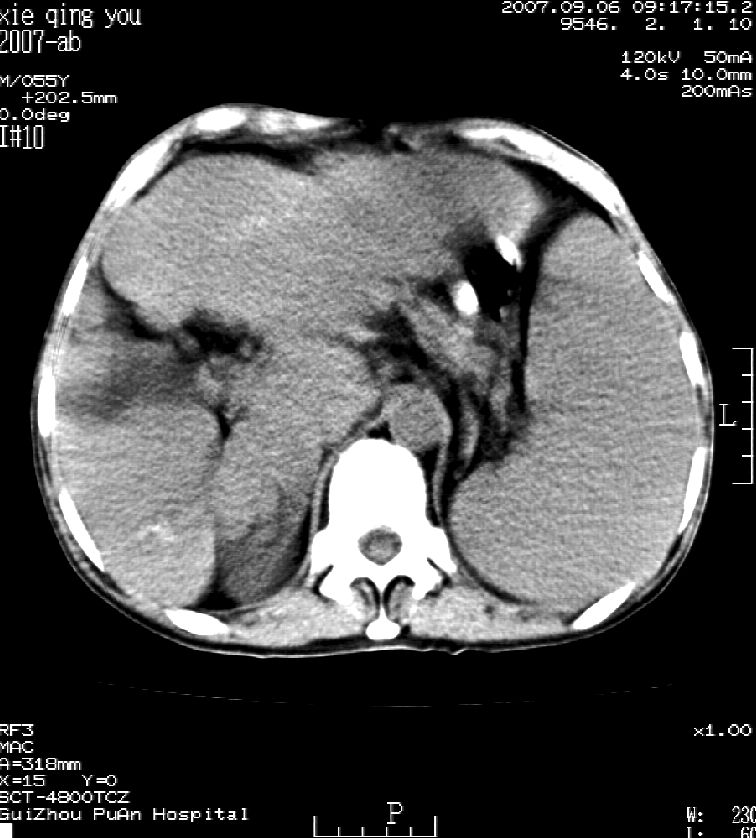

2007年9月片

因是普通ct不能做增强

这个病灶很有意思,怎么可能没有了呢?我考虑当时很可能是肝脏脓肿(b超示囊肿是有可能误诊的,因为影像表现都是低回声吗?),现在脓肿吸收了,肝脏萎缩,肝裂增宽了.别的肝叶代偿增大,不过现在左内叶的确有个占位,肝内多发结石,脾脏比以前大,不排除有肝硬化可能.建议增强扫描给于定性!!!!

肝硬化\\脾大,肝左叶肝癌可能性大,建议增强扫描.肝内胆管多发性结石.

1, 肝硬化,脾大;2,肝左叶肝癌可能性大,建议增强扫描.3,肝内胆管多发性结石.